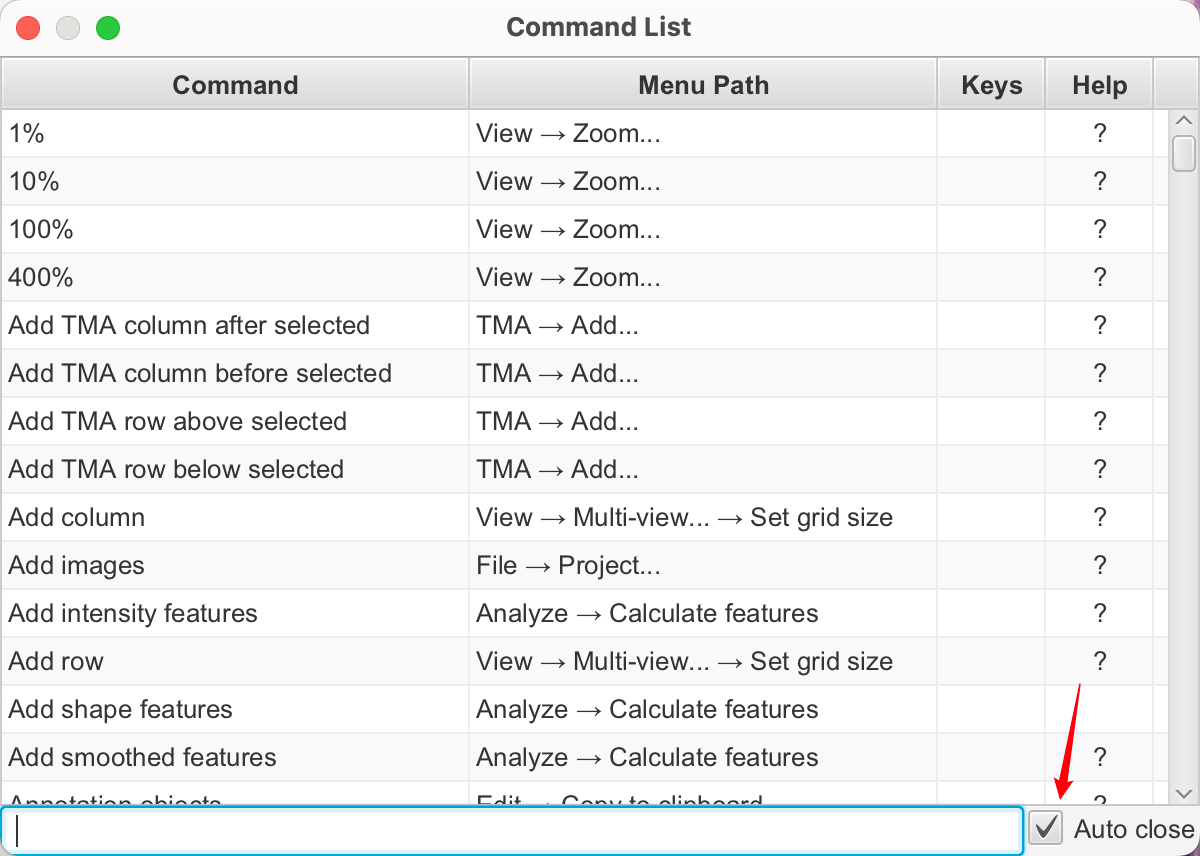

命令列表

您需要记住的最重要快捷键是Ctrl + L。这会打开命令列表(也位于“View ‣ Command List”下)。

然后,您可以开始键入您想要查找的任何内容的名称,并且只有匹配的命令会在您键入时显示。您可以以两种方式运行命令:

- 使用鼠标,通过双击

- 使用键盘,通过使用箭头键选择命令,然后按Enter键

命令列表现在还包括了大多数命令的简要帮助文本描述。

提示

如果您发现自己想要反复运行相同的命令,请取消勾选“自动关闭”框以保持命令列表打开。